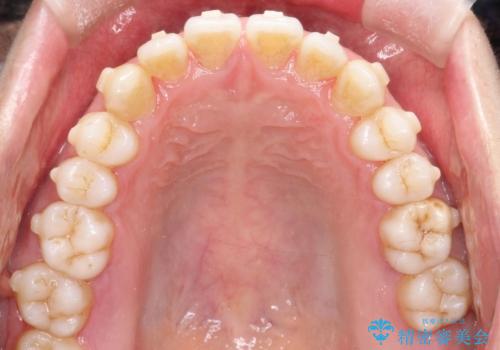

- 前歯のすきっ歯が気になると来院された患者様です。

前歯の隙間をマウスピース矯正(インビザライン)を使用して、閉じていきました。